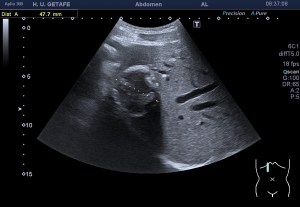

Al llegar al compartimento 6 me encuentro un tendón engrosado de tamaño y aspecto heterogéneo típico de afectación por tendinosis, con líquido en la vaina, te lo señala la imagen con flecha amarilla. Lo recorro y confirmo los hallazgos eje corto y eje largo, hago medidas y compruebo el doppler que marca Neovascularización asociada.

Observa las tres imágenes superiores, son muy ilustrativas, son comparativas de normalidad hallazgos patológicos, el izquierdo claramente patológico y el derecho claramente normal.